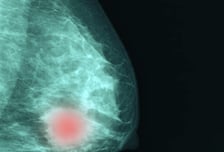

조기 유방암 환자, 재발 예측 점수 낮으면 안심? '이것' 높으면 표적항암 받아야

조기 유방암 환자에서 예후 진단 지표인 '온코타입Dx' 점수가 낮더라도, 암세포 활성도(Ki-67) 수치가 높다면 표적항암치료를 통한 적극적인 치료가 필요하다는 연구 결과가 발표됐다. 연세대 강남세브란스병원 유방외과 안성귀 교수, 서울아산병원 유방외과 이새별 교수, 한림대 동탄성심병원 유방외과 이장희 교수 공동 연구팀은 '유방암 환자에서의 Ki-67, 21-유전자 기반 재발 예측 점수(온코타입Dx), 호르몬 내성 및 생존에 대한 연구'를 진행했다. 임상 현장에서 온코타입Dx와 Ki-67은 조기 유방암 환자의 예후를 예측하고, 항암 치료 여부를 결정하는 대표적인 지표로 활용된다. 온코타입Dx 검사상 25점을 기준으로 항암 여부를 결정하며, 종양세포의 증식과 관련된 핵단백질인 Ki-67 지수를 통해 종양의 공격성을 예측한다. 특히 호르몬 수용체 양성/HER2 음성 유방암에서 Ki-67이 높을수록 암 재발 가능성이 높거나 예후가 좋지 않은 것으로 알려졌다. 앞서 진행된 연구들에서 Ki-